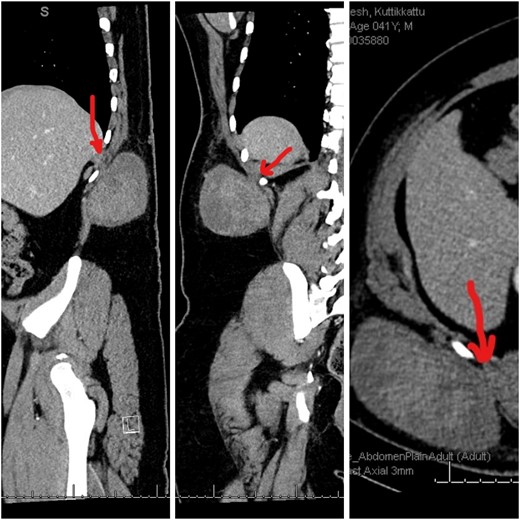

A 41-year-old male was diagnosed with a right flank swelling that was present for the past 2 years. Initially, the swelling was ~3 cm × 3 cm in size. There was a rapid increase in size since the past 6 months. Clinically, the patient had a right flank swelling measuring 35 cm × 25 cm in size (Fig. 1), which was soft in consistency and attached to the deeper muscular plane. A CT scan was done that revealed the same findings (Fig. 2).

CT images showing the heterogenous lesion in the right flank with the loss of fat plane between the lesion and the underlying muscle at one place.

Dedifferentiated liposarcoma and malignant fibrous histiocytoma [3] were initially considered in this patient. Rapidly progressive lympho proliferative lesions in the subcutaneous plane are extremely rare. The lesion has been present for 2 years with a recent rapid increase in size. Clinically and radiologically, it is seen in the subcutaneous plane with no deeper extension except for the attachment to the underlying muscle at one place (Fig. 2). Histopathology findings were that of a fibrous tissue with diffuse proliferation of mature plasma cells with prominent Mott cells. Immunohistochemistry studies were done, which revealed the following: AE1/AE3 (negative), MYO D1 (negative), Myogenin (negative), A1 Antitrypsin (positive) [4], A1 Anti chymotrypsin (positive), CD 45 (strongly positive), CD 68 (positive) [5], S 100 protein (negative) and Desmin (negative). The lesion also had mature plasma cells with a low Ki67 proliferation index. Immunoglobin Gene Rearrange V (Negative), MYD88 L265P Gene mutation (Negative), EBER (Negative), Kappa and Lambda ISH—plasma cells heavily skewed toward kappa light chain expression with EBER (Negative). Other markers like CD1a, CD19, CD56, CD86-PGM1, CD117, CD138, CD163, ALK, BRAF V600E, cyclin D1, Factor 13A, HHV8, IgG, IgG4, Langerin, MUM1, OCT2, PAX5 and S100 were all negative.